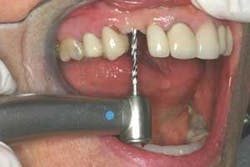

Figure 4 - Pilot drill for implant placement. A laser was used to create the soft tissue access for the pilot hole. The 1.8 mm diameter pilot drill was followed by the 2.5 mm diameter drill to depth, followed by the 3.0 mm drilled just short of final depth.